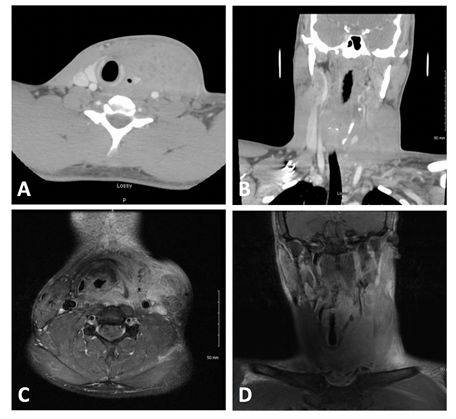

A 22-year-old African American male with no pertinent past medical, surgical or social history, presented to the emergency department with a 3-month history of progressively worsening left-sided neck swelling and pain. He had sustained blunt trauma to the neck just prior to the start of his symptoms. He was treated with a round of amoxicillin followed by steroids as an outpatient with minimal improvement in his symptoms. He eventually presented to the emergency department (ED) when the pain was significant enough to restrict his neck range of motion. Other associated symptoms included fevers, malaise, night sweats and a 30 pound weight loss. At presentation to the ED, he was noted to have a fever of 101.3 F and a large indurated, erythematous left neck. On exam, the area was tender to palpation and crossed from the anterior midline neck to the left posterior neck and down the left clavicular area. No fluctuance was appreciated. Neck range of motion was severely limited, particularly with head turn to the left. Flexible fiberoptic laryngoscope showed slight airway deviation to right with no other abnormalities. Work up demonstrated leukocytosis with a left shift and CT scan showed a large left neck mass causing slight airway deviation to the right with no obvious abscess formation (Figure 1A) (Figure 1B). MRI imaging demonstrated an enlarged contrast-enhancing left sternocleidomastoid mass extending medially to involve the left parapharyngeal space, visceral space, and left retropharyngeal space at the level of the thyroid cartilage (Figure 1C) (Figure 1D). Given the type B constitutional symptoms suggestive of an infectious process versus malignancy, empiric IV antibiotics (vancomycin, zosyn, and unasyn) were initiated. An ultrasound guided core needle biopsy was performed which was inconclusive. Quantiferon and HIV tests were negative. Given the lack of a diagnosis, decision was made to perform an incisional biopsy under general anesthesia on hospital day 5 at which time there was a central area of spontaneous seropurulent drainage. Incisional biopsies of the sternocleidomastoid muscle and cultures of the drainage were obtained. Surgical pathology demonstrated skeletal muscle and fibrous tissue with dense suppurative and chronic inflammation, suggestive of a reactive or inflammatory process. There was no evidence of malignancy. Cultures were consistent with Staphylococcus epidermidis and Propionibacterium acnes. Constellations of findings were suggestive of pyomyositis. The patient’s symptoms improved and he was discharged on day 10 with oral antibiotics. Patient did not return for his follow up appointments however he did endorse dramatic resolution of his swelling and symptoms by phone.

Figure 1 Complex 4.6 x 7.4 x 7.2 cm centrally necrotic enhancing mass centered about the inferior left sternocleidomastoid muscle causing slight airway deviation to the right. MRI shows mass extending medially to involve the left parapharyngeal space, visceral space, and left retropharyngeal space at the level of the thyroid cartilage. A) Axial CT   B) Coronal CT   C) Axial MRI   D) Coronal MRI.